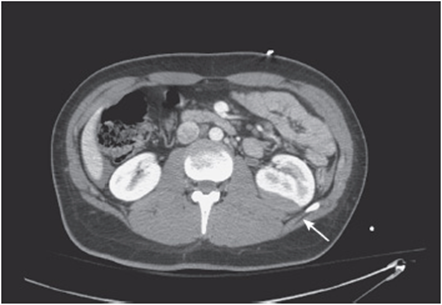

vi. Check the spleen:

• Check for lacerations (eg, trauma), enlargement (malignancy, hyper-splenism), or abnormal fluid collections (eg, liver abscess or cyst) (see Figure 56-6).

Figure 56-6. Liver fluid collection suspicious for liver abscess.